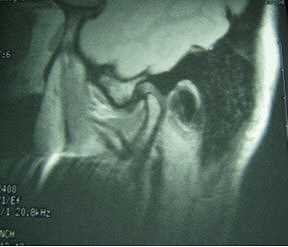

![]() |

Same patient. Postop lateral displacement of right disk. Pain improved in both joints; clicking resolved in left joint only. Images courtesy of Dr. Jessica Lee.